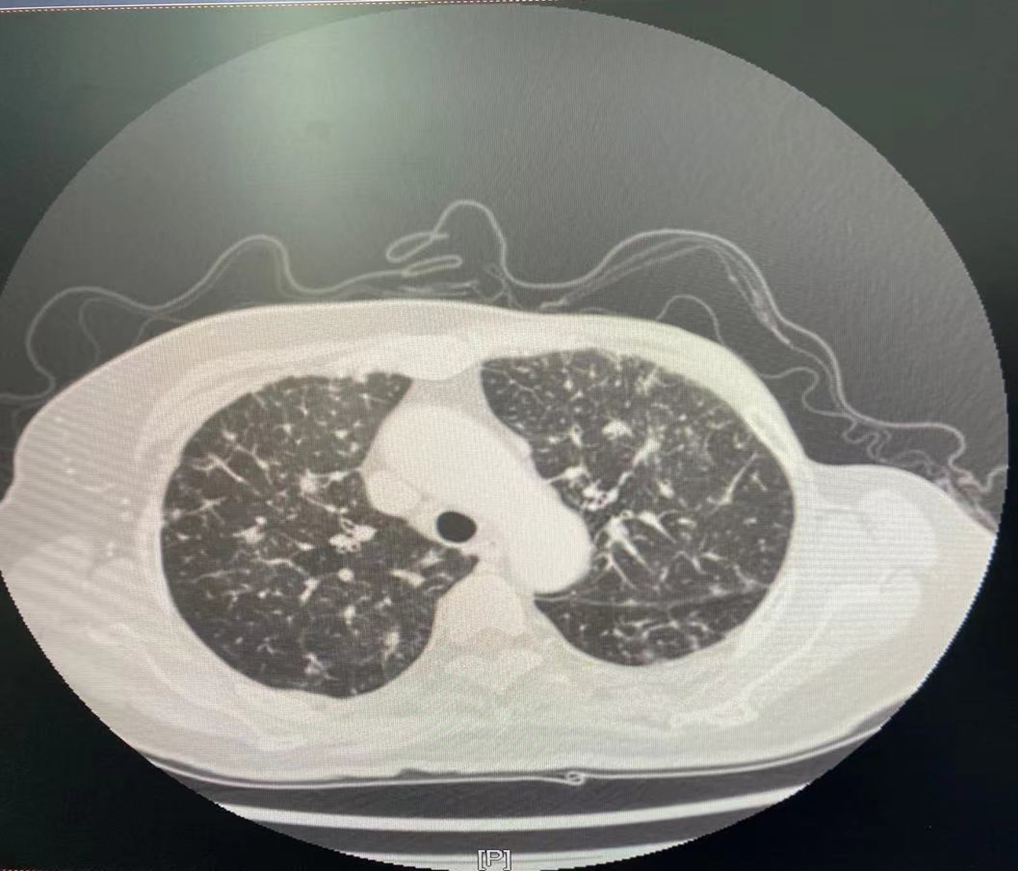

图4.肺窗

2021年4月7日双肺示:转移可能。